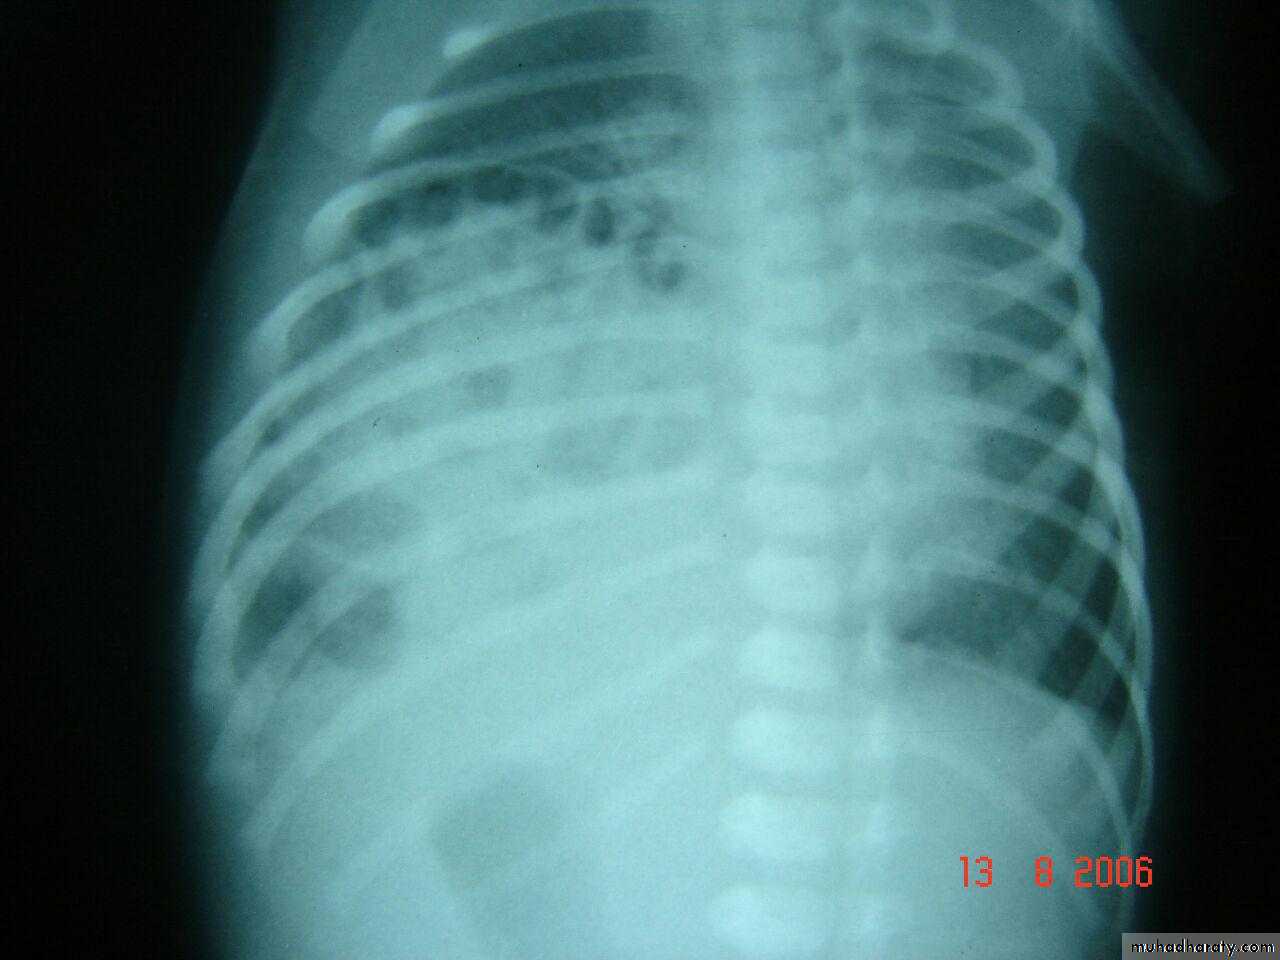

X ray of wrist showing cupping fraying splaying

Dx >>> rickettwo labrotary investigation 1. alkaline phosphatase elevation

2. s.calicium low or normal

ricket